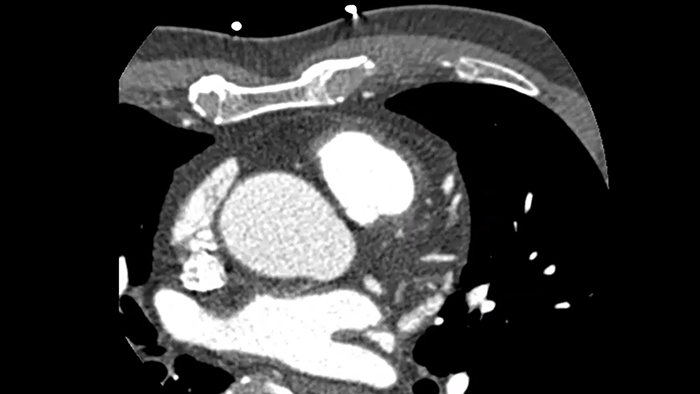

Supere los desafíos de las imágenes cardíacas

Imagenología cardíaca libre de movimiento que mejora la calidad de la imagen a altas frecuencias cardíacas

ContinueAdvanced motion-compensation reconstruction for motion-free cardiac scanning with improved coronary analysis